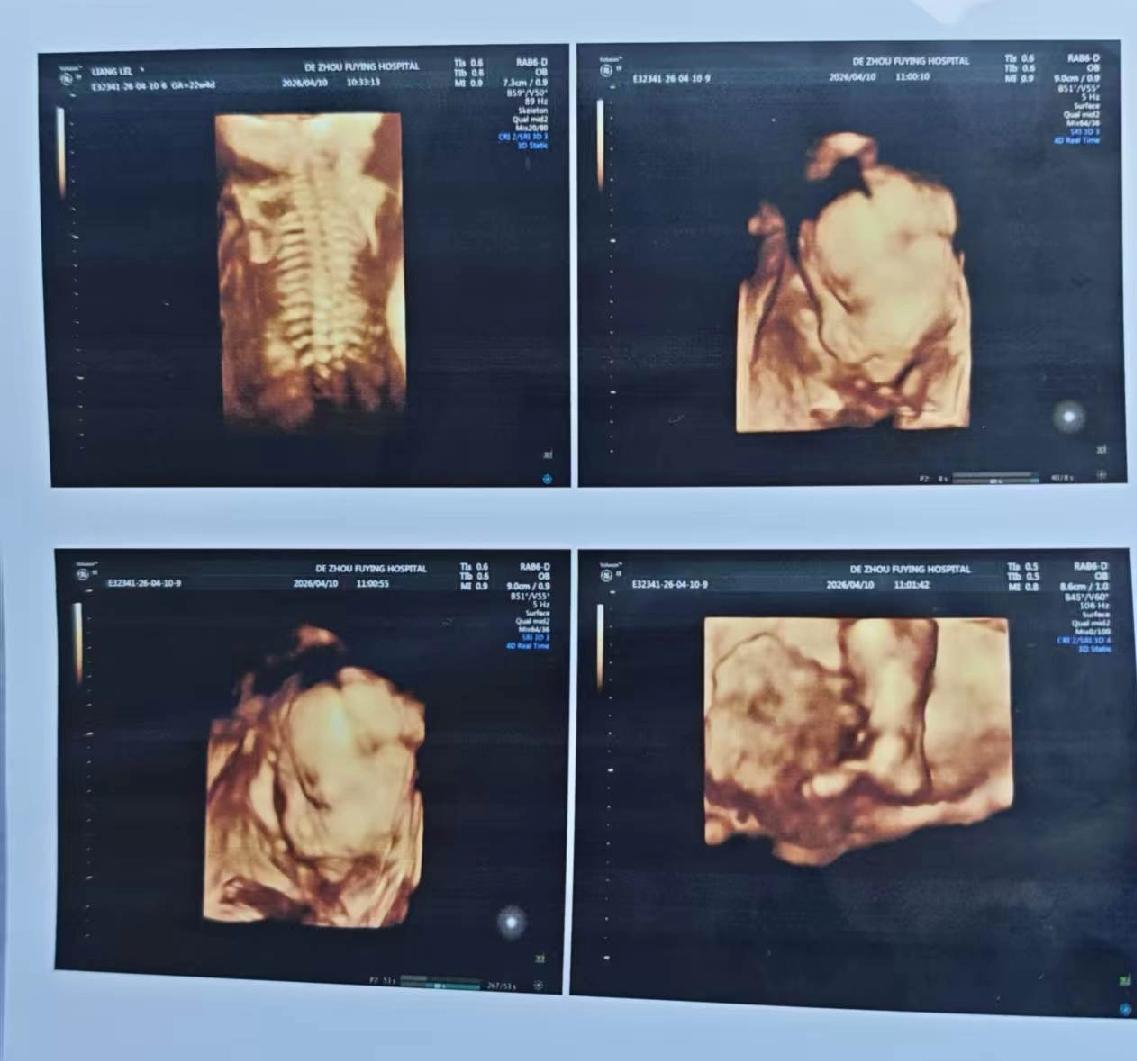

轮到儿媳妇了,第一次宝宝也是不配合,趴着看不清。

第二次进去,宝宝真翻过身来了。

给大家看一下,猜猜是小棉袄还是皮夹克。